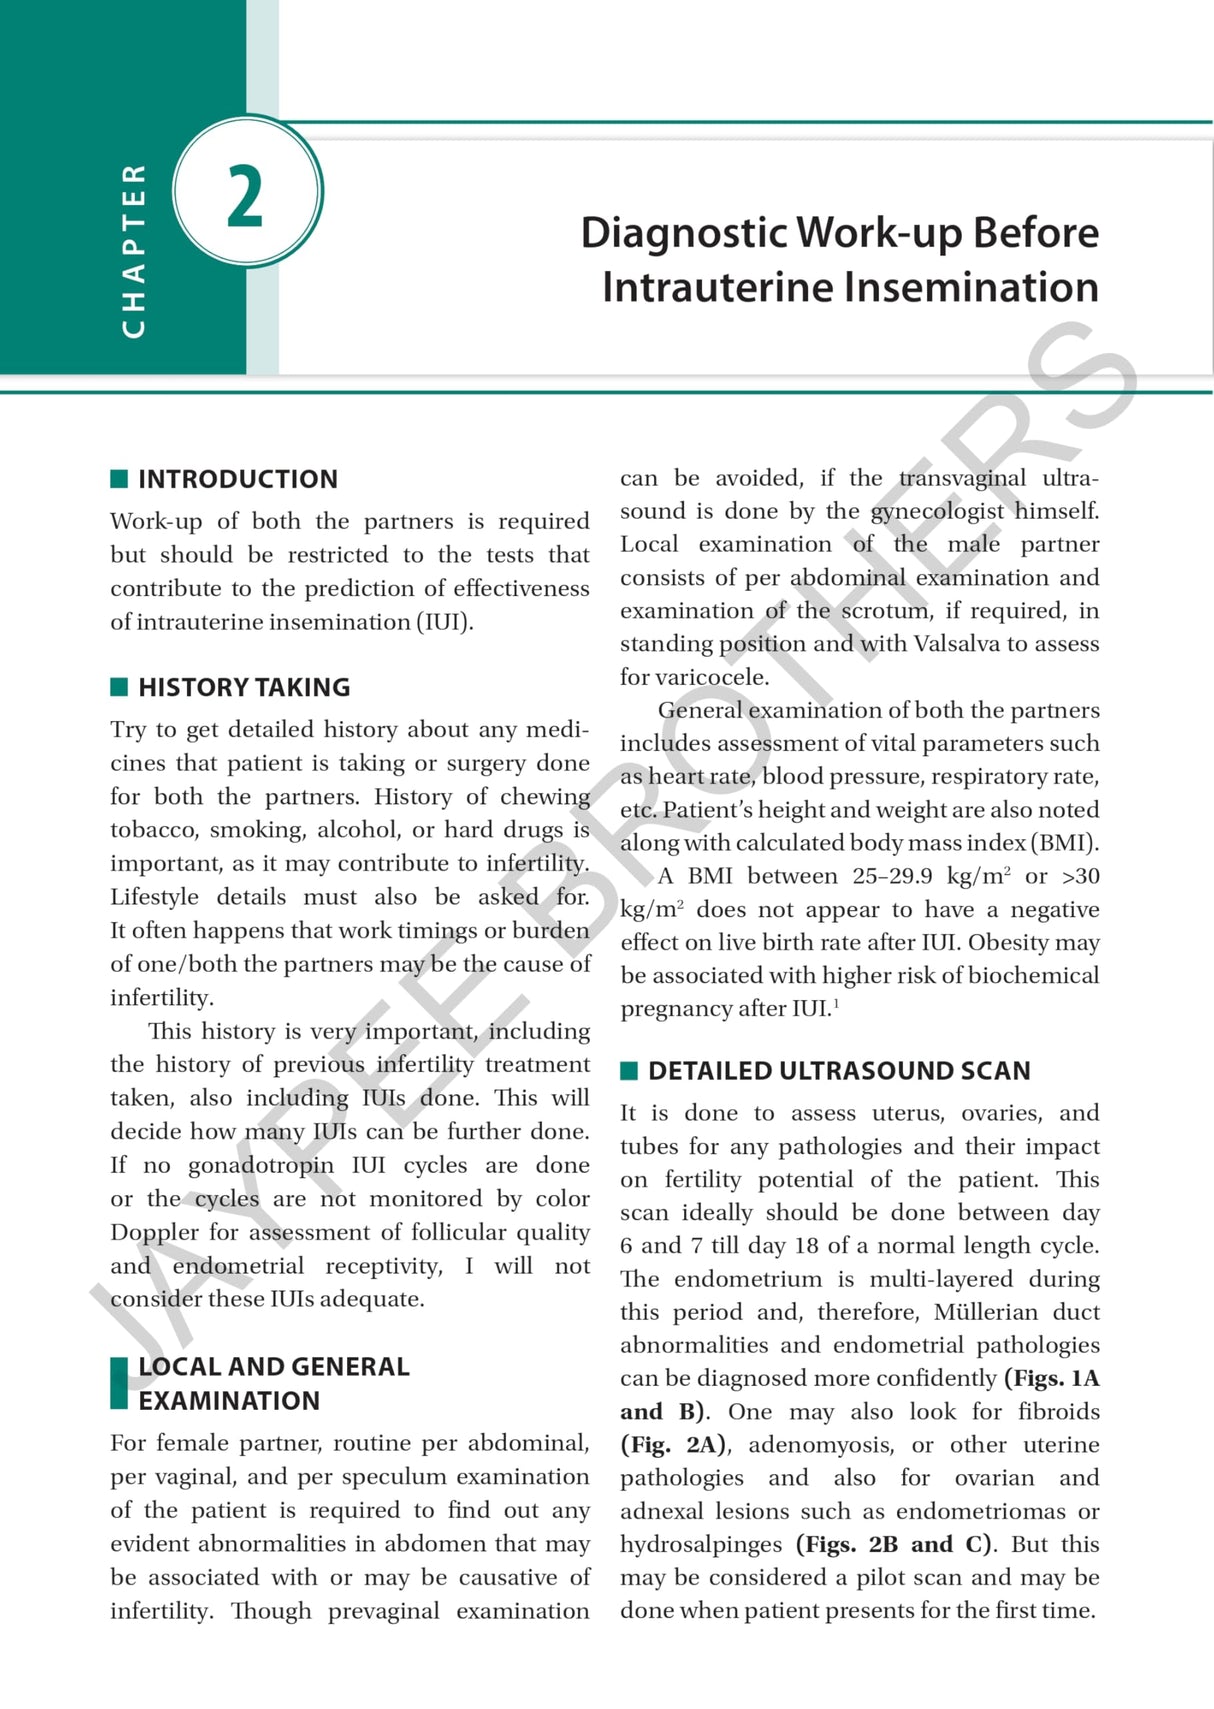

Details: Intrauterine Insemination (IUI), also known as artificial insemination, is a type of fertility treatment in which the better quality sperm are selected and then injected directly into the womb during ovulation. It is more natural and cost-effective than In Vitro Fertilisation (IVF), but it is also less successful in achieving a pregnancy.

Authored by renowned experts in the field, this book is a step-by-step guide to the complete process of IUI for practising and trainee gynaecologists.

Beginning with discussion on counselling and diagnostic work-up before IUI, the next chapters cover indications and ultrasound. The following sections examine ovulation, timing of IUI, techniques, luteal phase support, complications, and factors affecting success. The final chapter discusses sperm preparation.

The text is further enhanced by clinical images and figures.